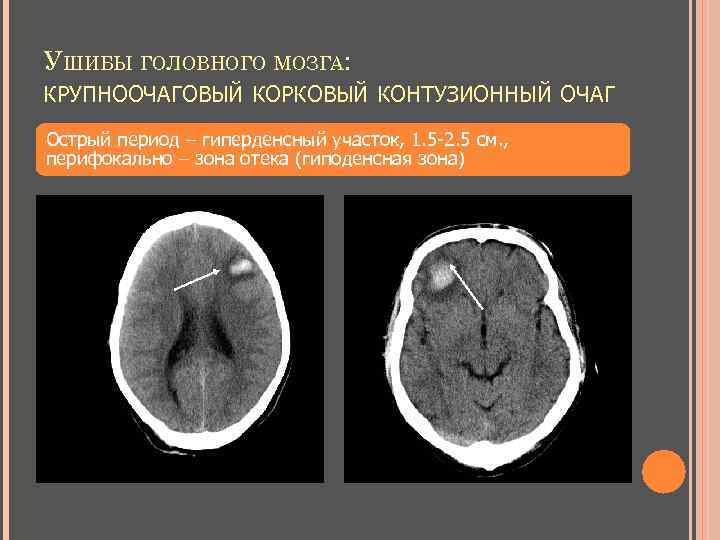

УШИБЫ ГОЛОВНОГО МОЗГА: КРУПНООЧАГОВЫЙ КОРКОВЫЙ КОНТУЗИОННЫЙ ОЧАГ Острый период – гиперденсный участок, 1. 5 -2. 5 см. , перифокально – зона отека (гиподенсная зона)